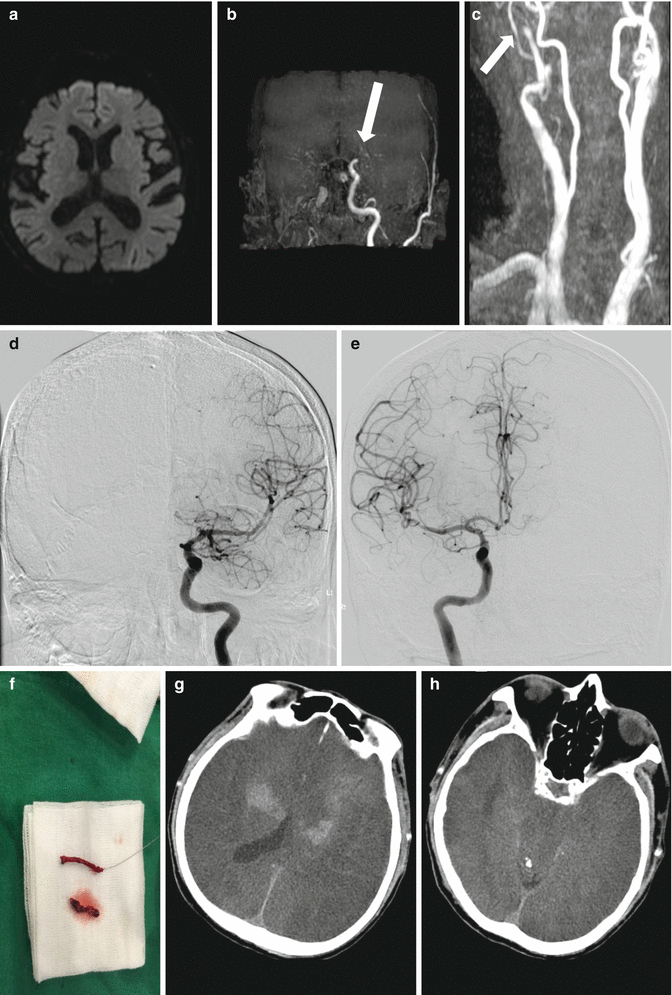

Fig. 3.2

A case of missed stroke diagnosis. An 85-year-old man with lost consciousness was transferred from general hospital. Neurologist was delayed 4 h after symptom onset because primary assessment was syncope, but recovery of mentality was delayed. Initial neurological examination revealed semicomatose mental status with decorticated posture and bilateral extensor Babinski reflex. Brain MR imaging with diffusion-weighted image showed slight increased signal intensity involving both cerebral hemispheres (a). MR angiography revealed the occlusion of left middle cerebral artery and right internal carotid artery at petrous segment (b, c). Emergent endovascular thrombectomy successfully recanalized both occlude vessels (d, e) and extracted red thrombi (f), but his mentation was not recovered and followed brain CT revealed massive brain edema and hemorrhagic transformation involving both cerebral hemispheres (g, h). He died 5 days after symptom onset